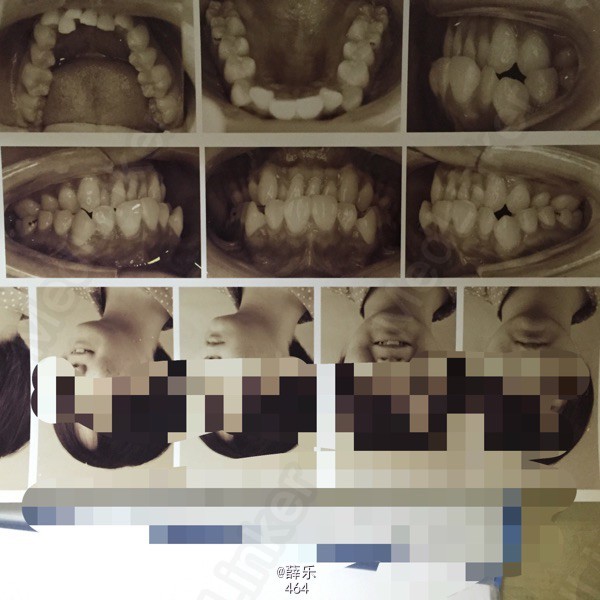

查体 辅查

恒牙列,牙列式17~27,37~47。双侧磨牙中性关系,上下牙列中度拥挤,13、23唇侧低位,38、48近中阻生,侧观呈直面型,上下前牙较直立

诊断:安氏1类错牙合伴牙列拥挤 建议:正畸治疗 处理:1.取研究模型 2.血液检查 3.全景片+侧位片+面像检查 4.约会诊